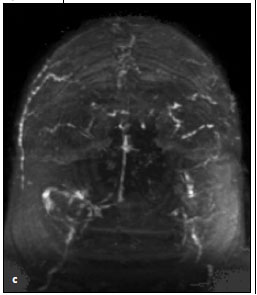

Brain magnetic resonance venography (C) was performed to rule out cerebral venous thrombosis. The test showed dural venous sinus thrombus of the bilateral transverse sinuses and superior sagittal sinus with resultant bilateral hemorrhagic cortical venous infarctions. A diagnosis of cerebral venous sinus thrombosis (CVST) was made, and heparin therapy was started. Thrombolysis was not initiated because in this setting there is no evidence that the clinical outcome is better with thrombolytics and the risk of bleeding is greater. Coagulation disorders were ruled out as a possible cause for CVST. Protein C activity was 80%; protein S activity, 71%; and antithrombin III, 100%. Results of tests for factor V Leiden mutation, prothrombin gene mutation, and antiphospholipid antibodies were negative. The patient's neurological condition improved once heparin therapy was initiated, and she was subsequently discharged to a nursing home with a prescription for warfarin.